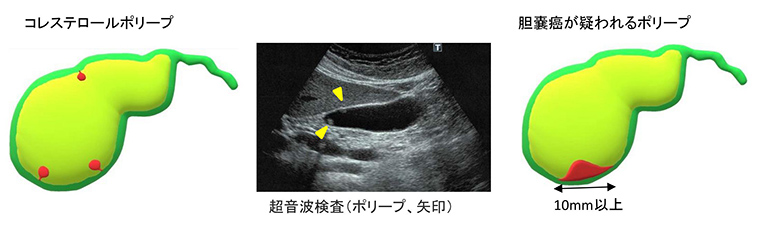

胆嚢ポリープ

胆嚢内にできる良性腫瘍ですが、大きさが1cm以上の場合や増大傾向を認める場合には悪性(胆嚢癌)である可能性が若干高くなります。

そのため、これらは手術により切除した実物によって判断する必要があります。

一方で、大きさ5mm以下の小さなポリープやコレステロールポリープ(胆汁に含まれるコレステロールの沈着によりできるもの)は3~6ヶ月毎の経過観察でよく、急いで手術をする必要はありません。